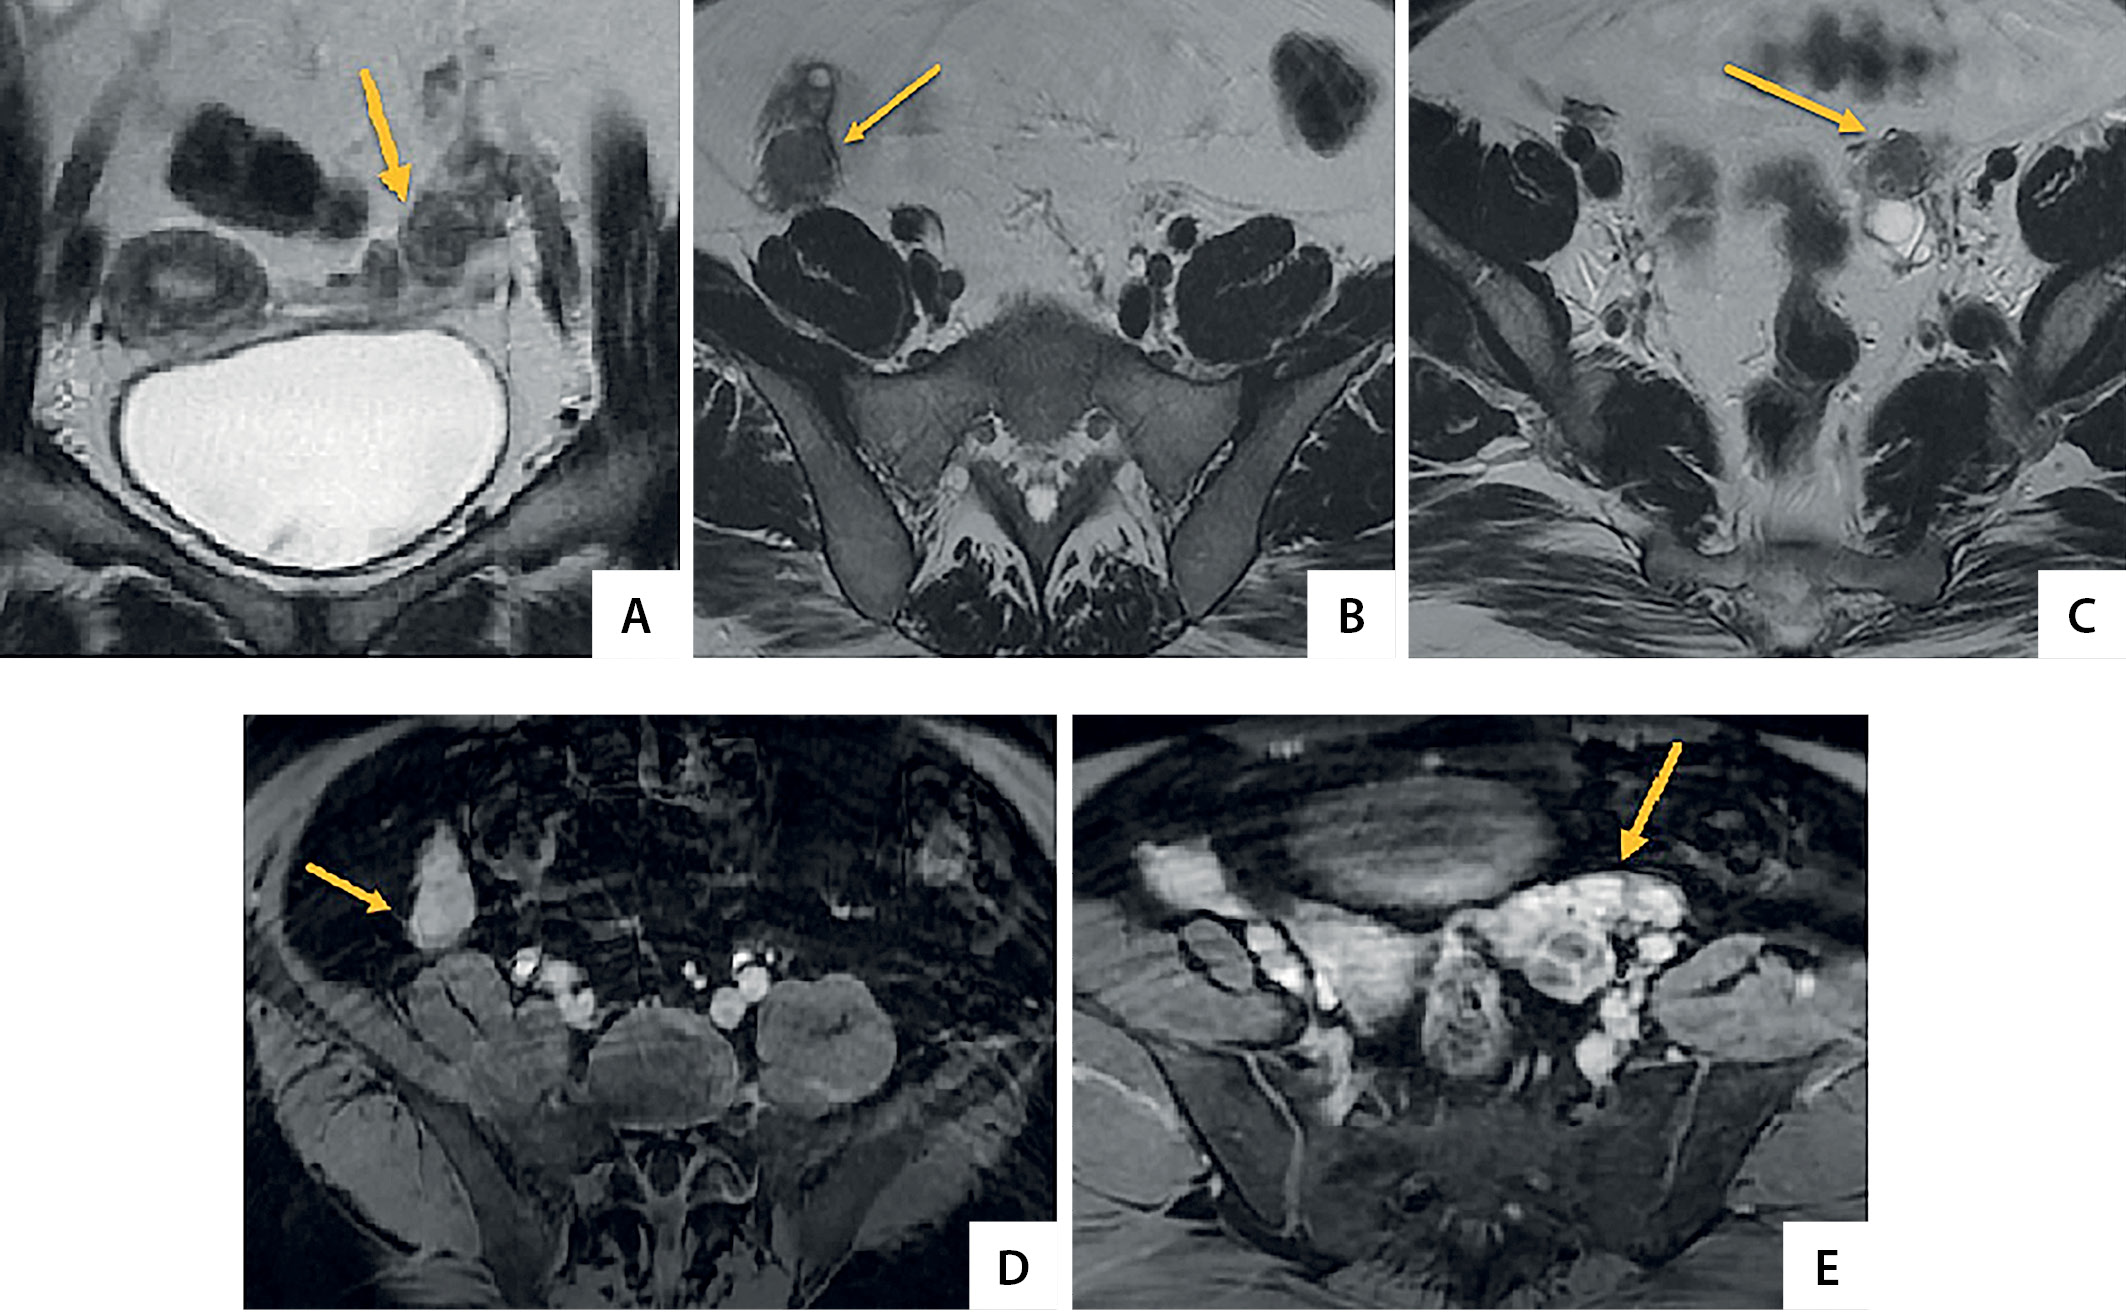

Для уточнения структурных изменений яичников проведена МРТ органов малого таза: яичники размерами: справа 47×37×22 мм, с наличием в структуре мелких фолликулярных кист до 7 мм; слева 32×37×19 мм, с наличием в структуре фолликулярных кист до 18 мм. В обоих яичниках визуализируются солидные образования неправильной формы, с четкими контурами (справа ровными, слева неровными), размерами справа 44×21×17 мм, слева максимальной протяженностью 40×31×14 мм (состоит из трех узлов до 15 мм, до 10 мм и до 8 мм соответственно), при контрастном усилении активно, несколько неоднородно накапливающие контрастный препарат. Наружные подвздошные, паховые лимфатические узлы множественные, не увеличены (до 8 мм). Заключение: МР-картина гиперваскулярных солидных образований в обоих яичниках — с учетом данных анамнеза, можно предположить эктопированную надпочечниковую ткань (OART); количественная лимфаденопатия (рис. 1).

Рисунок 1. Магнитно-резонансные томограммы малого таза пациентки N. В обоих яичниках определяются солидные образования с четкими, неровными контурами, при контрастном усилении образования активно накапливают контрастное вещество (стрелки): А — Т2-взвешенное изображение (ВИ), корональная плоскость (левый яичник); В — Т2-ВИ, аксиальная плоскость (правый яичник); С — Т2-ВИ, аксиальная плоскость (левый яичник); D — Т1-ВИ с подавлением сигнала от жировой ткани с контрастным усилением, аксиальная плоскость (правый яичник); E — Т1-ВИ с подавлением сигнала от жировой ткани с контрастным усилением, аксиальная плоскость (левый яичник).

2. Рисунок 1. Магнитно-резонансные томограммы малого таза пациентки N. В обоих яичниках определяются солидные образования с четкими, неровными контурами, при контрастном усилении образования активно накапливают контрастное вещество (стрелки): А — Т2-взвешенное изображение (ВИ), корональная плоскость (левый яичник); В — Т2-ВИ, аксиальная плоскость (правый яичник); С — Т2-ВИ, аксиальная плоскость (левый яичник); D — Т1-ВИ с подавлением сигнала от жировой ткани с контрастным усилением, аксиальная плоскость (правый яичник); E — Т1-ВИ с подавлением сигнала от жировой ткани с контрастным усилением, аксиальная плоскость (левый яичник).